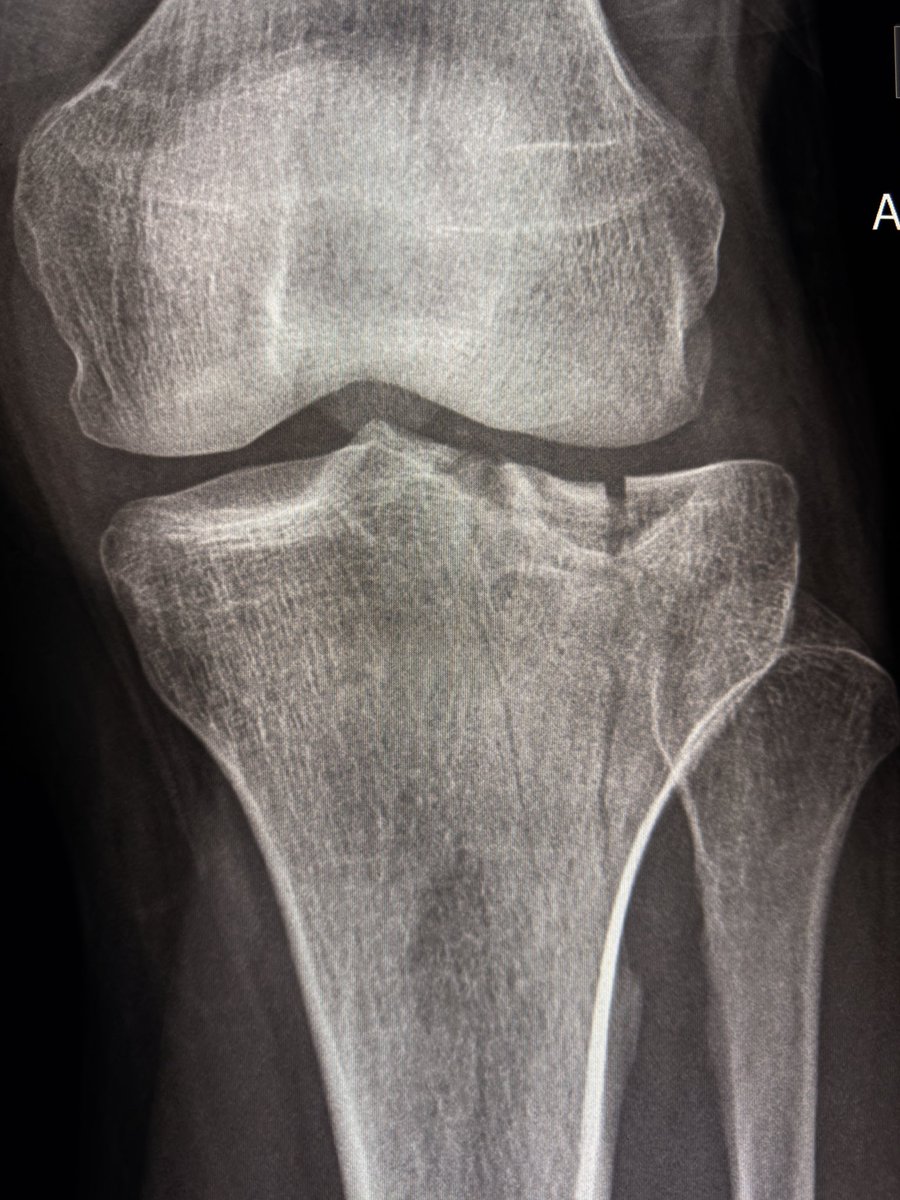

This case showed a fibrous coalition of Medial accessory talocalcaneal articulation at the level of the posterior sustentaculum tali, between the Talus and Calcaneus.

Talar beak is a marker of restricted subtalar motion, not a diagnosis. In a young patient, actively search for a subtalar coalition.